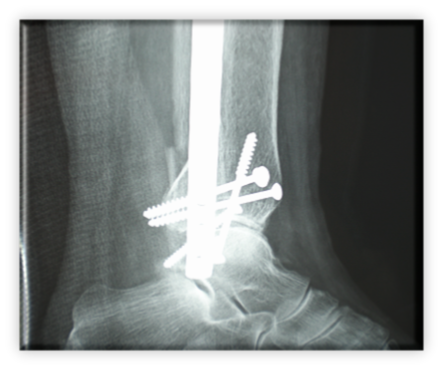

Κάταγμα κάτω πέρατος περόνης (έξω σφυρού) παρεκτοπισθέν με ταυτόχρονη παρεκτόπιση προς τα έξω του αστραγάλου. Αντιμετωπίστηκε με ανοικτή ανάταξη και εσωτερική οστεοσύνθεση με πλάκα – βίδες και μία διακαταγματική βίδα συμπίεσης